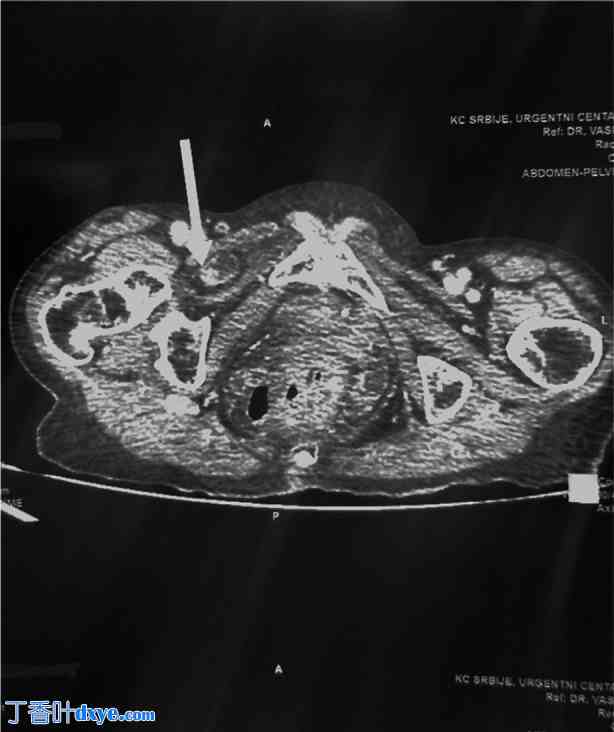

一名83岁女性因右下腹部急性发作、绞痛性腹痛,并伴有间歇性恶心、呕吐和便秘而到急诊就诊。检查时,患者体质虚弱,营养不良,并伴有哮喘导致的肺功能受损。腹部检查发现下腹部有压痛,但未触及肿块。肠鸣音亢进。鉴于临床怀疑肠梗阻,腹部超声检查显示盆腔内小肠袢扩张,作者决定进行CT扫描。患者立即接受了腹部和盆腔CT扫描;结果显示右侧肠梗阻,近端小肠袢直径最大可达28毫米。远端小肠袢出现塌陷,提示继发于疝气的肠梗阻(图1)。

图1

CT扫描显示小肠嵌顿(箭头所示)。